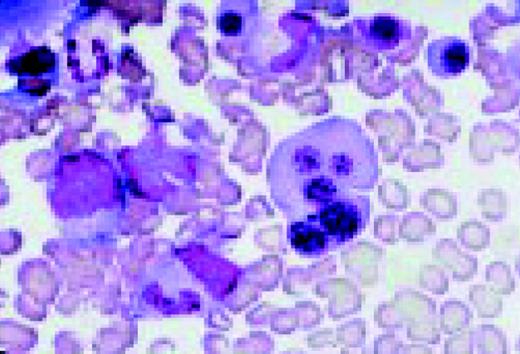

Striking dysgranulopoiesis associated with AIDS, bone marrow aspirate, May-Gruenwald-Giemsa. One of the macropolycytes is likely to be tetraploid (92 chromosomes) and the other to have 138 chromosomes. A normal neutrophil is shown in the lower left for comparison.FIG52

Slide L53